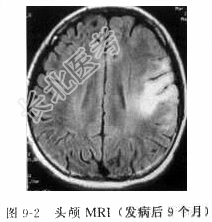

患者女性,14岁,右利手。因“发作性右侧肢体抽搐22个月,右侧肢体无力16个月”入院。患者于22个月前无明显诱因出现发作性头右偏,不能言语,持续约1min,当时无意识障碍。于当地医院检查行头颅CT及MRI检查颅内未见明显异常,脑电图提示边缘状态脑电图。患者2天后出现右口角持续性抽搐,于北京某医院就诊,诊断癫痫,予“卡马西平(得理多)”口服治疗后好转。18个月前出现右上肢持续性抽搐,再次前往北京某医院就诊,MRI印象左侧额叶病变,首先考虑炎症性病变,脑电图为高度不正常儿童脑电图,左侧半球为著。17个月前右上肢转为间断性抽搐,并逐步出现右下肢持续性抖动,卧位时明显。并逐步出现右侧面肌无力、上肢无力以手部为甚,而后出现下肢无力,呈进行性加重。1个月前再次于北京某医院诊断考虑线粒体脑肌病可能,予肌肉活检后排除该病。目前此类症状发作频繁,发作形式表现为:头右偏,右口角及上下肢抽搐,发作时意识清楚,言语稍欠流利,抽搐时间短则数十秒,长则2min,发作约每日二十余次。药物治疗方面:由单一应用得理多到逐渐联合应用托吡酯(妥秦)、拉莫二嗪等多种抗癫痫药物联合应用。现口服得理多、妥泰和拉莫三嗪,仍不能满意控制癫痫发作。患者发病前3个月上呼吸道感染(感冒)发热,最高体温为39℃,发热持续4天后好转。患者发病以来,智力逐渐下降,较同龄儿童明显下降。体格检查T37.0℃,R19次/min,P80次/min,BP120/60mmHg。专科查体:神志清楚,言语欠流利,右侧鼻唇沟,浅口角左侧歪斜,伸舌稍右偏,耸肩右侧稍力弱。右手屈曲挛缩,右下肢内翻畸形,右上肢近端肌力4级,远端3级,右下肢肌力4+级,左侧肢体肌力5级,左侧腱反射正常存在,右侧肱二头肌、肱三头肌、膝腱反射及跟腱反射亢进,右侧Babinski征、Cordon征、Chaddoch征、Hoffman征阳性。辅助检查头颅MRI检查(发病后5个月)(图9-1):左侧额叶沿中央沟两侧脑灰质可见长T1长T2信号、Flair高信号,局部脑组织略肿胀,脑沟略浅。头颅MRI(发病后9个月)(图9-2):左颞叶皮质及皮质下多发片状长Tl长T2信号、Flair高信号,与发病后5个月比较左额叶病变范围扩大,左颞叶为新出现病变。头颅MRI(发病后19个月)(图9-3):与发病后9个月相比,①左额颞进展性病灶,白质逐步受累,左内侧颞叶、扣带回额内侧回、旁中央小叶逐渐受累;②左侧半球进行性脑萎缩,以额颞叶为主。